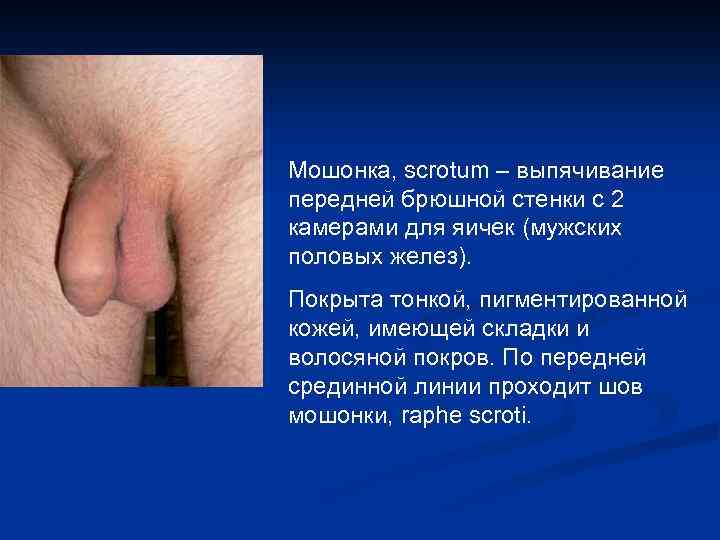

Мошонка, scrotum – выпячивание передней брюшной стенки с 2 камерами для яичек (мужских половых желез). Покрыта тонкой, пигментированной кожей, имеющей складки и волосяной покров. По передней срединной линии проходит шов мошонки, raphe scroti.

Мошонка, scrotum – выпячивание передней брюшной стенки с 2 камерами для яичек (мужских половых желез). Покрыта тонкой, пигментированной кожей, имеющей складки и волосяной покров. По передней срединной линии проходит шов мошонки, raphe scroti.